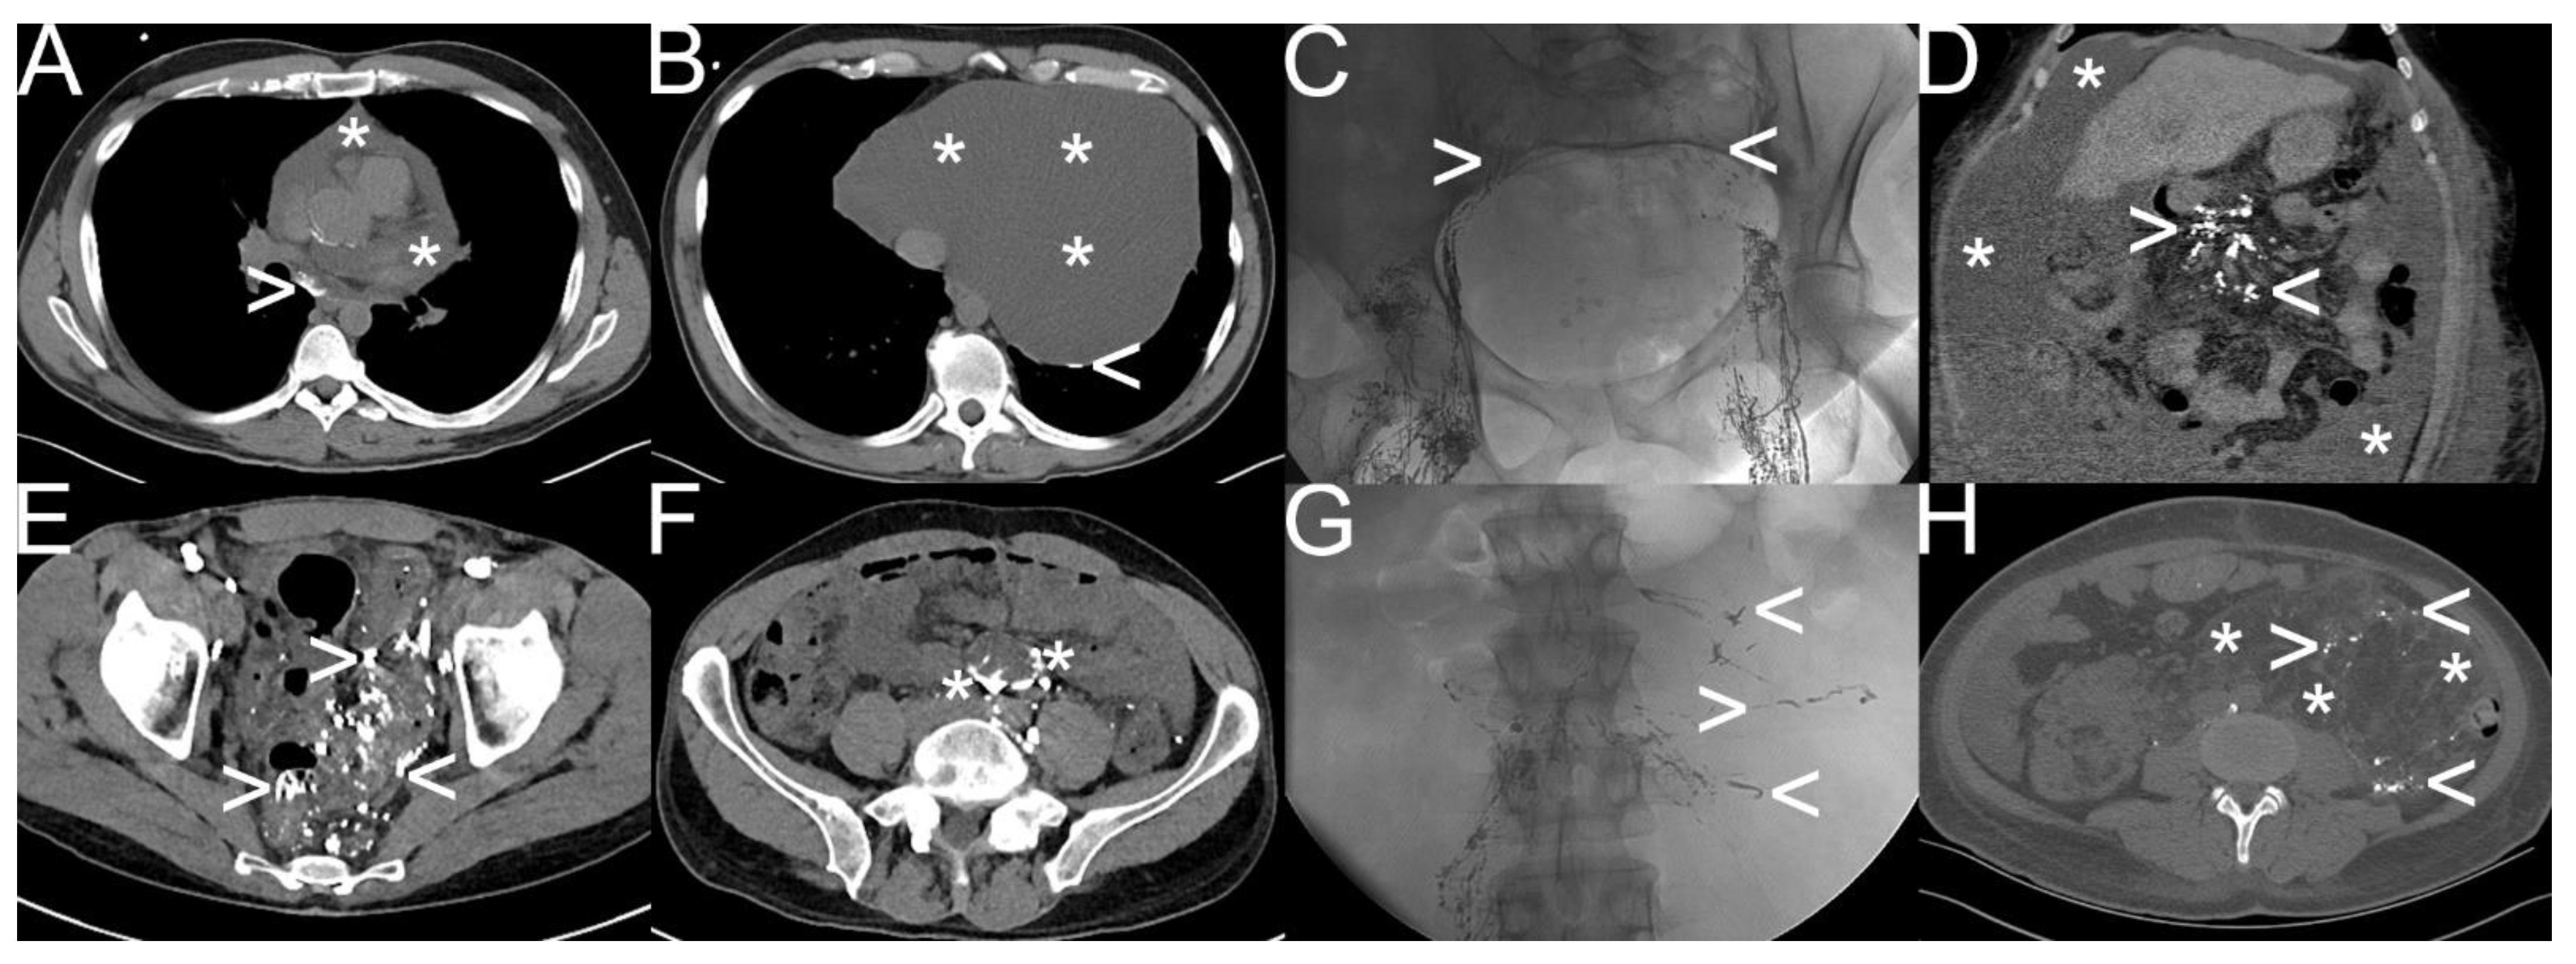

Figure 4.

Different types of spontaneous lymphatic fistulas detected by “conventional lymphangiography“. Note: (A,B) etiologically unclear chylopericardium (white asterisk) with pathologic accumulation and extravasation of oil-containing contrast material (white arrowhead); (C,D) liver cirrhosis with chylous ascites (6000–8000 mL per day) (white asterisk) as a result of lymphatic congestion (white arrowhead) due to severe portal hypertension; (E,F) diffuse lymphatic malformation in the sigmoid and rectum visualized with oil-containing contrast material (white arrowhead) after bilateral “transpedal lymphangiography” due to reversed lymphatic run-off at the cisterna chyli flowing into the mesenteric trunk (white asterisk); (G,H) combined chylothorax, chylaskos, and chyloretroperitoneaum in a patient with tuberous sclerosis complex with atypical lymphatic run-off in the retroperitoneum as well (white arrowhead) due to giant angiomyolipoma (white asterisk).